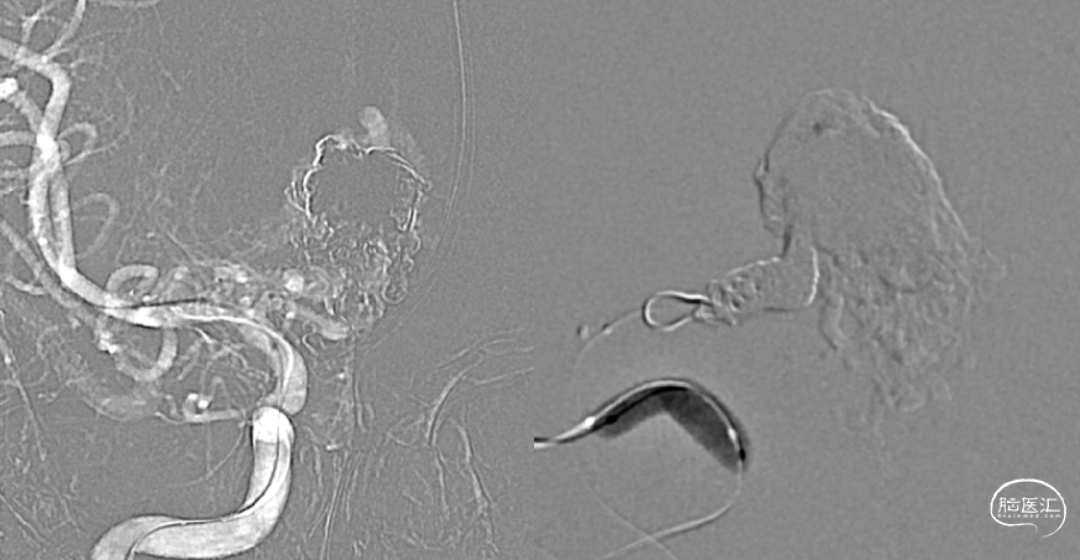

7个月前第一次静脉入路栓塞

术后即刻造影

经静脉入路超选到位

经Echlon10微导管填入弹簧圈做塞子

经Apllo微导管注入Onyx胶